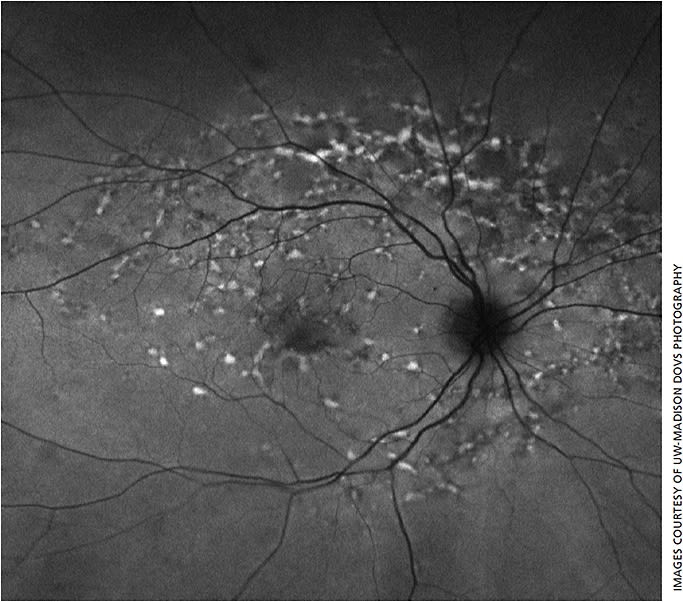

Classical clinical findings of STGD1 include the presence of irregular yellowish flecks, sometimes described as pisciform, at the level of the retinal pigment epithelium (RPE) in the macula that can extend out into the periphery (Figure 1, page 26). These flecks are variable in shape, size and distribution and are created by excessive accumulation of lipofuscin in the RPE. Macular atrophy, macular pigment mottling and macula depigmentation can also develop. Initially, clinical exam may show a normal fundus or just mild foveal pigment mottling changes.11 Also, up to one third of children may not initially present with flecks.10

Ocular imaging techniques can provide further information useful in diagnosis, characterization and monitoring of STGD1. Fluorescein angiography (FA) in STGD1 can show the classic “dark choroid,” with reduced fluorescence from the choroid due to blockage by lipofuscin in the RPE, although this is not present in all patients.13 Fundus autofluorescence (FAF), which can be done quickly and noninvasively in the clinic, has largely replaced FA in the assessment of STGD1. FAF shows hyperfluorescence in lipofuscin-laden areas, sometimes before they are apparent clinically, and hypofluorescence in areas of macular atrophy due to loss of RPE (Figure 2).14 Subtypes of FAF may help predict disease progression.15 Also, spectral domain optical coherence tomography (SD-OCT) can help show alterations of outer retinal structure in the macula.11 Other research imaging modalities, such as adaptive optics, have given new insights to cellular structural changes at the level of the photoreceptor mosaic in STGD1.16,17